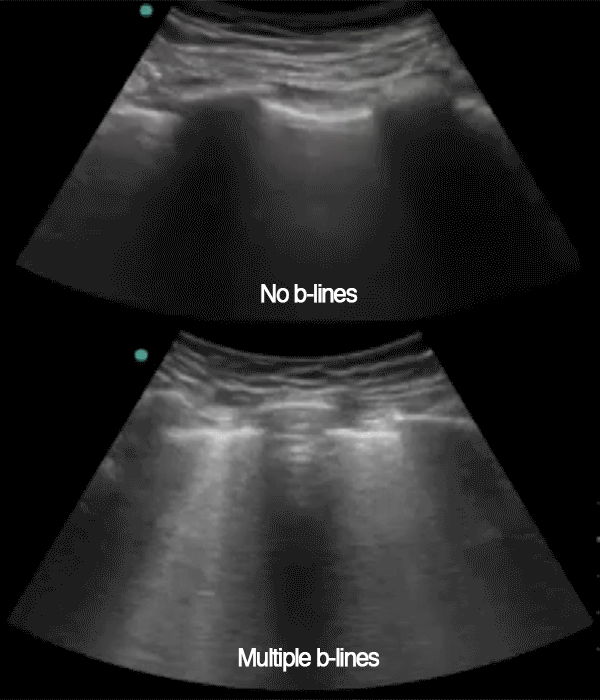

The following ultrasonographic signs are suggestive of pulmonary edema:

• Multiple B-lines (>2) between two costae in more than one view bilaterally

The following ultrasonographic signs rule out pulmonary edema:

• Absence of multiple B-lines between two costae in more than one view bilaterally